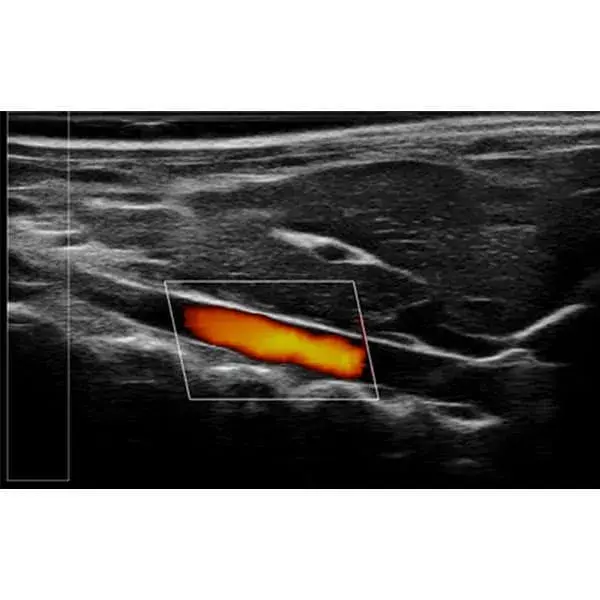

The RevoSilex F30/F60 delivers ultra-high-resolution, non-invasive imaging tailored for small animal models including mice, rabbits, and zebrafish. Equipped with advanced ultra-high-frequency technology and color Doppler functionality, it enables real-time assessment of cardiovascular performance, tumor vascularization, and physiological dynamics. Designed for applications in cardiovascular research, oncology, developmental biology, and drug discovery, its compact and portable architecture supports easy handling and reliable performance in longitudinal and repeat imaging studies.